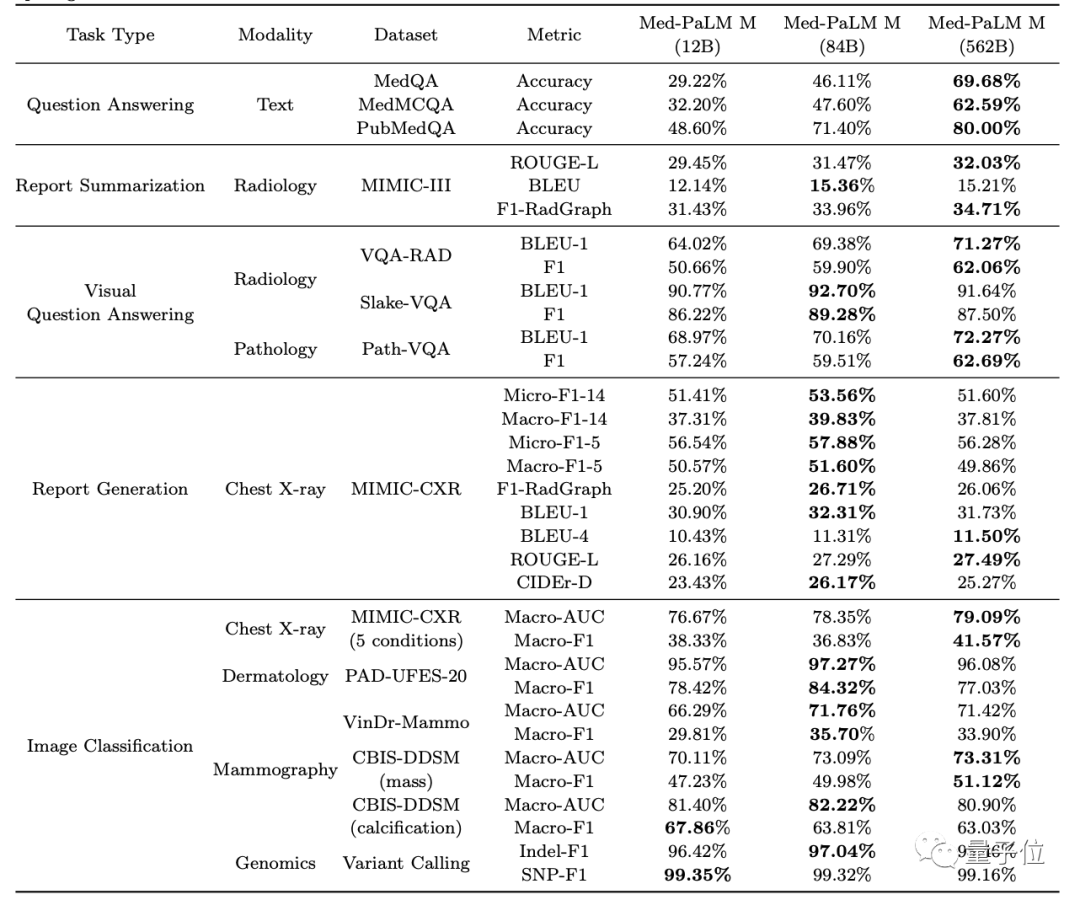

(2)在scale实验中,三个不同规模的Med-PaLM M对各类任务的影响各不相同:

粗略来看,对于纯语言任务和需要调整的多模式任务来说,模型越大越好;但对图像分类和胸部X光报告生成任务来说,84B的效果比562B表现反而更好一些。